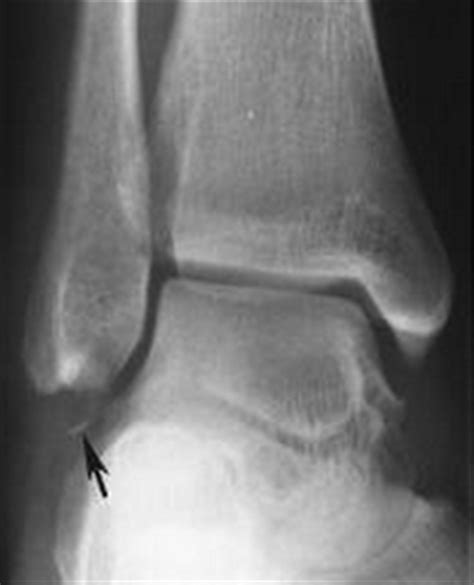

Identifying the root cause of chronic ankle pain is the first step in developing an effective treatment plan. A thorough medical evaluation, including imaging tests such as X-rays, MRIs, or CT scans, can help diagnose the underlying condition.

Diagnosing Chronic Ankle Pain

Diagnosing chronic ankle pain involves a comprehensive evaluation by a healthcare professional. The diagnostic process typically includes:

• Medical history and physical examination

• Imaging tests such as X-rays, MRIs, or CT scans

• Blood tests to rule out infections or inflammatory conditions

• Nerve conduction studies to assess nerve function

Based on the findings, your healthcare provider will develop a personalized treatment plan tailored to your specific needs.